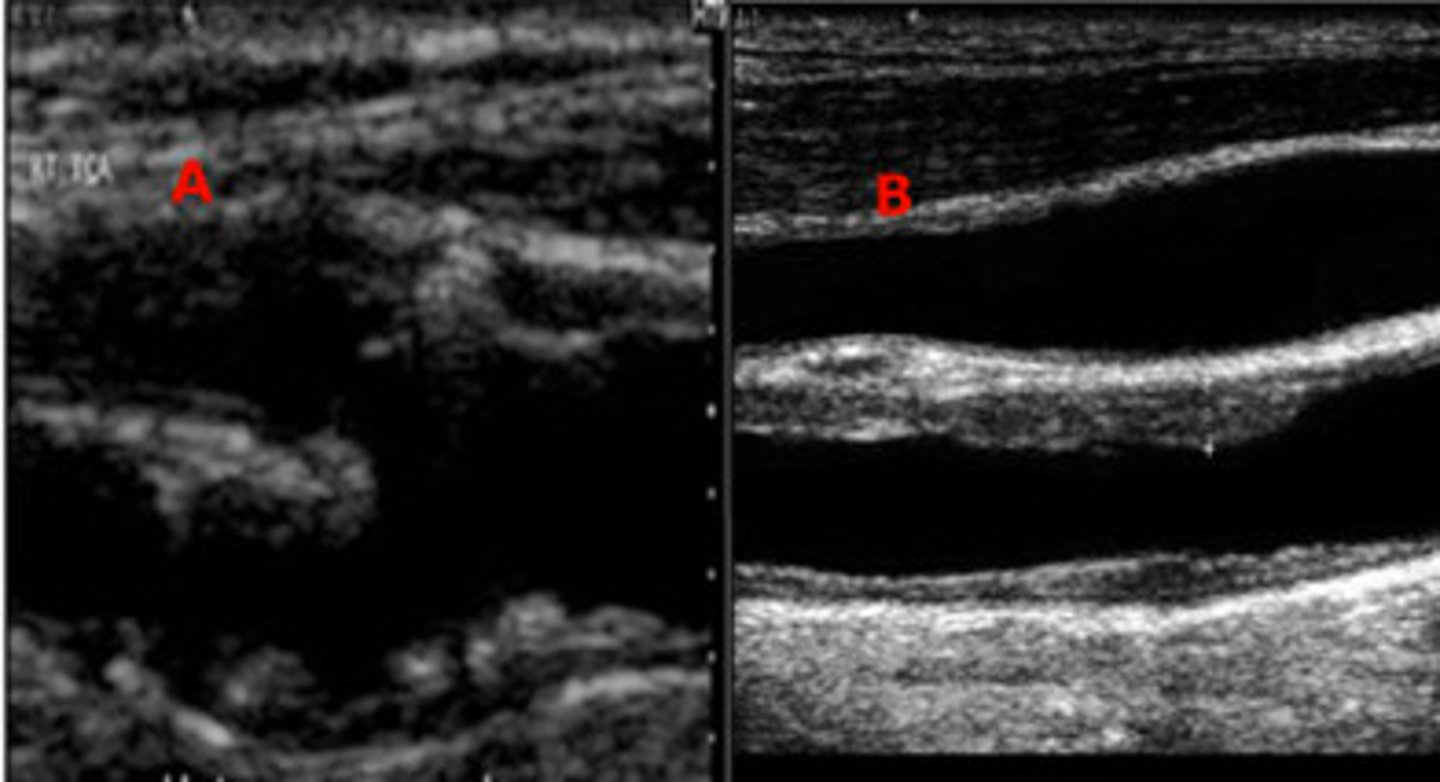

Which one of the two images represents a plaque that is at risk of embolization?

Image A

Image B